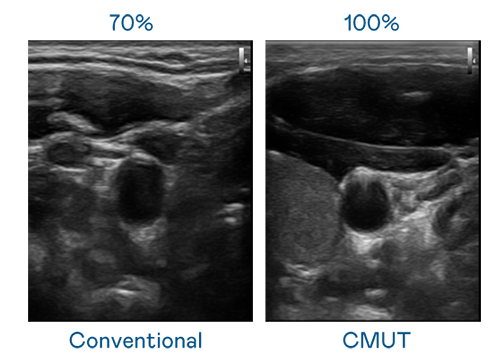

CMUT 技术是一种用电容式微机电元件来产生超音波讯号的技术。与传统 PZT 压电式技术相比,CMUT 频宽增加 30%,更宽频的超音波讯号让影像解析度大幅提升,是实现高影像品质医疗超音波扫描、促进精准医疗发展的关键技术。

超音波影像的解析度高低,首先取决于探头能发出的讯号频宽。九游会·AG CMUT 可提供高清晰的超音波讯号,提供高频宽、高灵敏度、影像纹理细节更高的超音波影像,协助医护人员缩短影像判读时间及利用精准的医疗影像进行诊断。